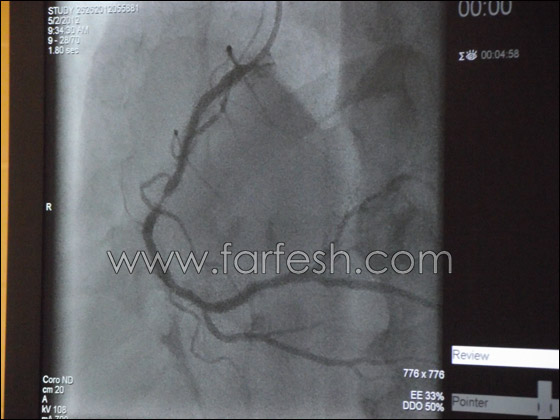

تجرى عملية القسطرة حيث يحدث تصلب في الشرايين وتكوّن الجلطة وانسدادها بشكل جزئي أو كلّي ومفاجئ، ولكن الحالة الأمثل لإجراء عملية القسطرة هي في حالة الإصابة بالنوبة القلبية، التي يكون فيها العامل الزمني مهم جدا لمنع حدوث ضرر في عضلة القلب، لذلك فإن المصاب بنوبة أو بجلطة، يصل مباشرة من سيارة الإسعاف إلى غرفة القسطرة، التي يعمل فيها اطباء مناوبون على مدار الساعة، ويتم على الفور فتح الشريان حيث حدثت الجلطة، ويتم اعادة جريان الدم لتقليل الضرر الذي قد يصيب عضلة القلب. وهنا يؤكد د. خالد سليمان ان كل دقيقة هي مهمة في هذه المرحلة. من جهة أخرى فإن هذا النوع من الجلطات المفاجئة قد يسبب السكتة القلبية، عندها ينبغي صعق المريض بالصدمة الكهربائية لإعادة تشغيل عضلة القلب ومن ثم نقله إلى المستشفى بأقصى سرعة.